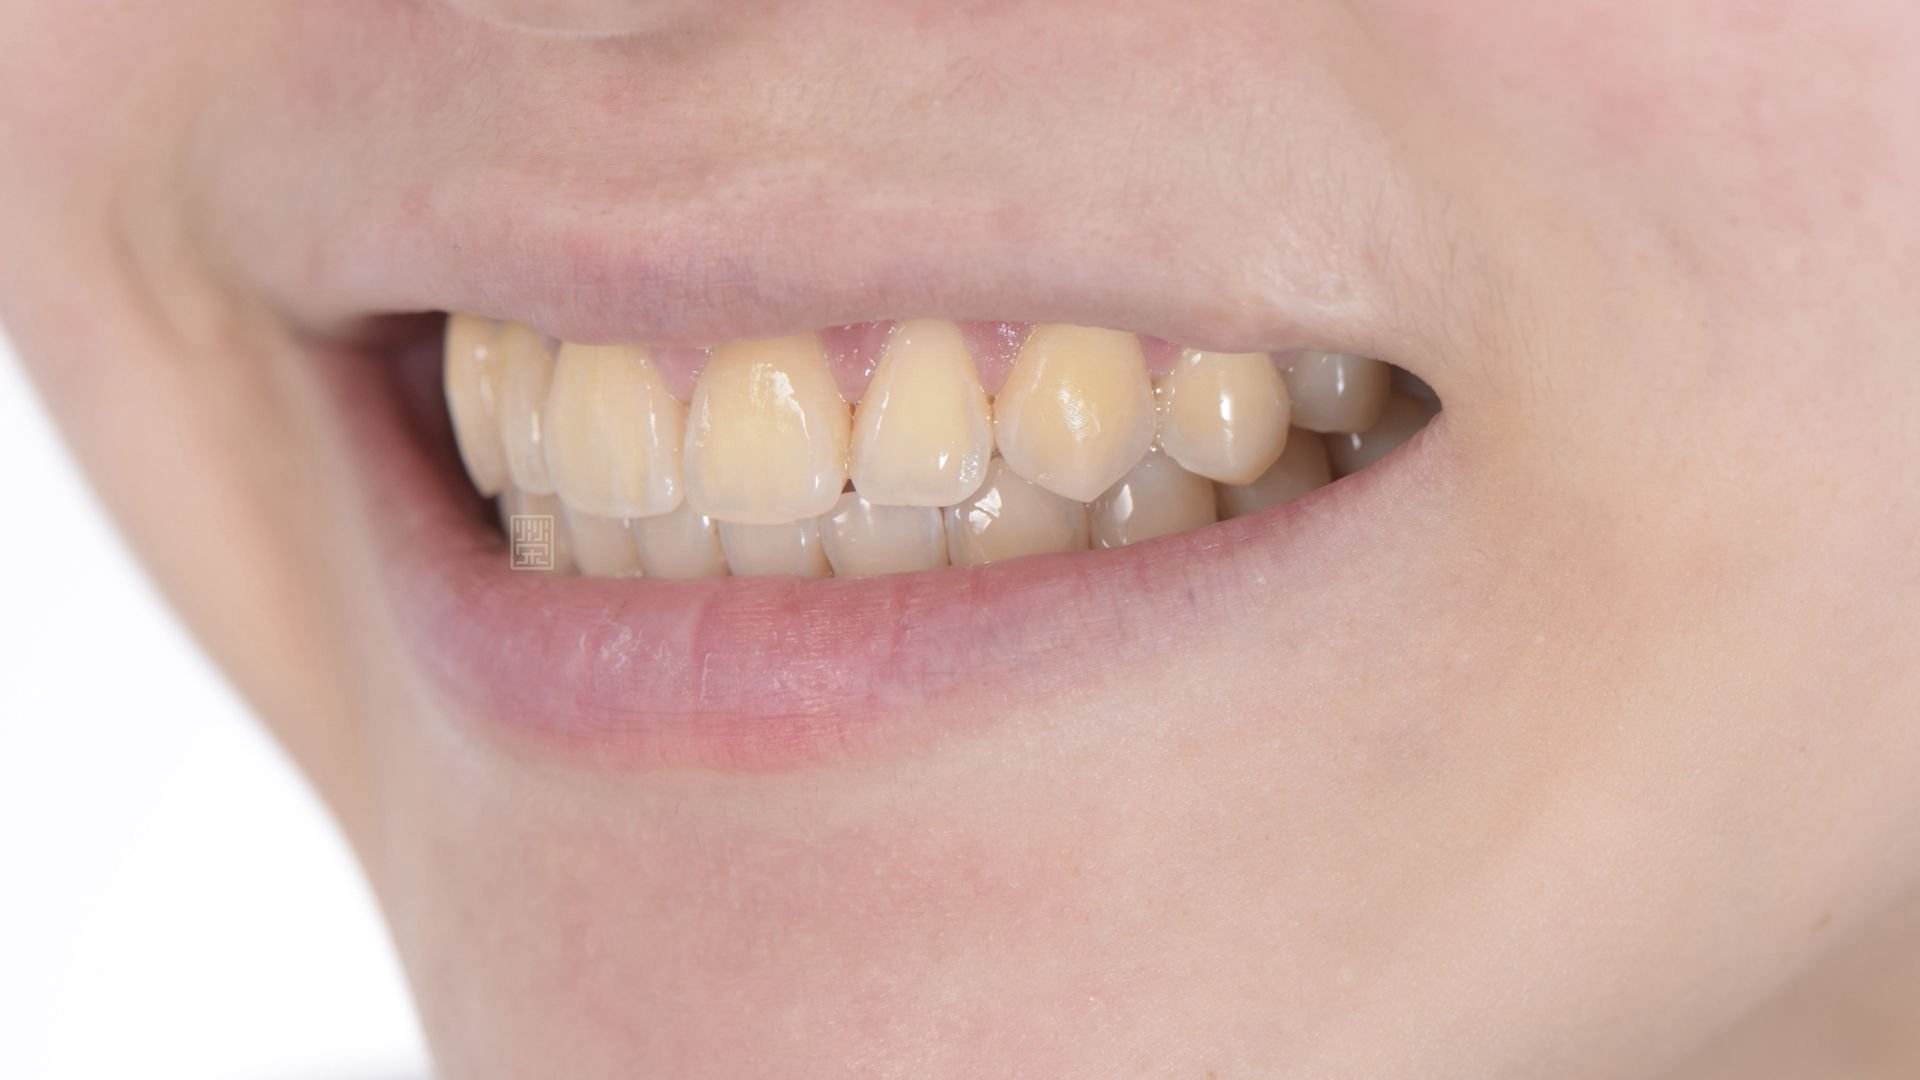

全瓷冠、植牙全瓷冠完成